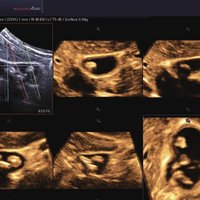

Das Samsung Accuvix A30 ist ein hochwertiges Ultraschallsystem, das mit seiner 3D-Technologie herausragende Ergebnisse ermöglicht. Das Sonographiegerät besitzt 5 Sondenanschlüsse und ist mit 20 unterschiedlichen Schallköpfen kompatibel. Mit dem A30 können Schallköpfe vom Typ Konvex, Mikrokonvex, 3D-Konvex, CW, Phased Array, Linear und Endokavitär verwendet werden. Bei zwei der Sonden handelt es sich um S-VUE Ultraschallsonden, die durch ihre höhere Bandbreite noch feinere Scans erzeugen.

Das Ultraschallsystem hebt sich besonders durch seine 3D-Technologie wie die Face Auto Detection für detaillierte Ultraschallbilder von Föten oder das Volume Shade Imaging, das sich auf die lebensnahe Darstellung von Schattierungen und Hauttönen fokussiert, ab. Mit weiteren wertvollen Technologien wie dem ElastoScan™ werden Tumore schneller erfasst und durch die HD Volumen Bildgebung sowie das DMR+™ eine erstklassige Bildqualität erzielt.

• FAD™, die Face Auto Detection, stellt das Gesicht eines Fötus besonders detailliert dar. Überflüssige Daten werden entfernt und ein besonders realistisches Bild gezeichnet.

• Volume Shade Imaging, kurz VSI™, visualisiert ein 3D-Bild, das Hauttöne und Schattierungen auf ein qualitativ neues Niveau hebt.